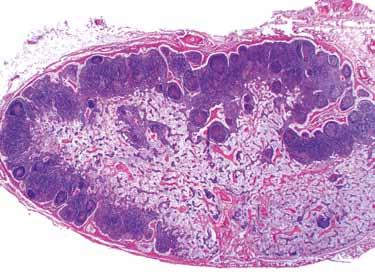

Obr. 1.5 a Histologický řez dětským thymem: septa vazivové tkáně (1), kůra (2), dřeň (3); b Hassalova tělíska (1); c thymus dospělého člověka. Zbytky tkáně thymu: dřeň (1), kůra (2), Hassalova tělíska (3), tuková a pojivová tkáň (4). [L 111]

monů k involuci thymu, takže u dospělých najdeme jen zbytky kůry a dřeně, zbylou hmotu thymu tvoří převážně tuk a pojivová tkáň (► obr. 1.5 c).